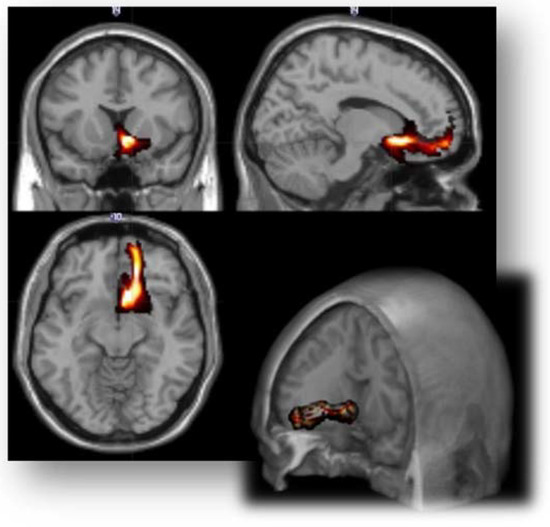

2.4. Region of Interest

- For each side, vaIC, daIC and pIC ROIs were obtained by dividing the entire available ROIs of insular cortex in the Harvard-Oxford Cortical Structural Atlas [91], based on its connectivity [92]. DTI pre-processing and probabilistic tractography were performed using the software modules provided in the FMRIB Software Library (FSL, http://fsl.fmrib.ox.ac.uk/fsl, accessed on 15 July 2017).

2.5. Probabilistic Tractography